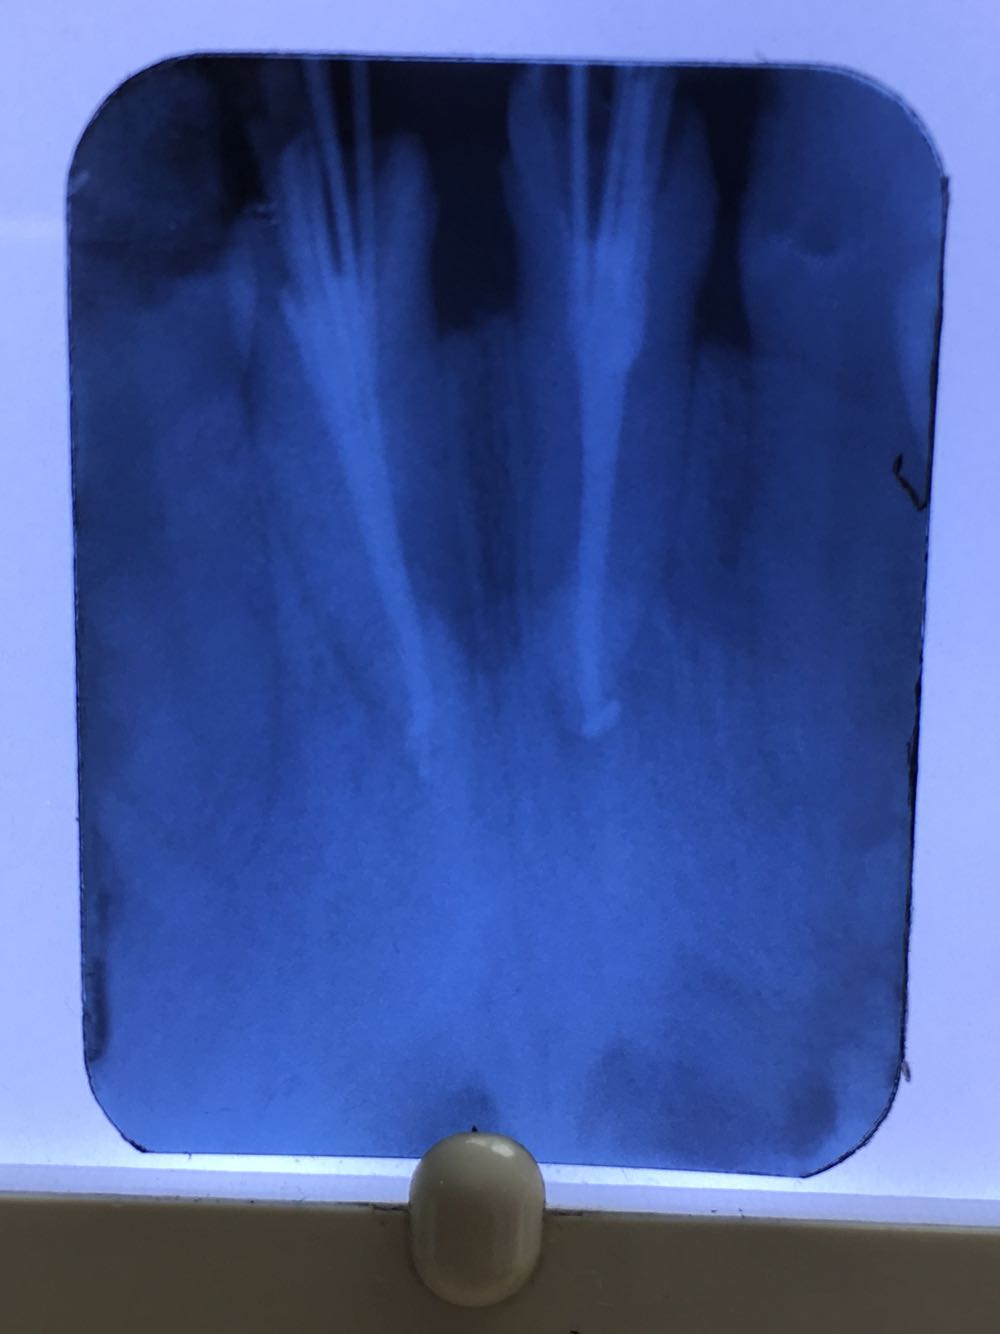

查:11,21残根无松动,根管内空虚。既往曾镶桩冠牙十多年。X线片示未做根管治疗,11根内可见约3毫米充填物。

11.21残根;治疗方案拟行根管治疗后桩冠修复